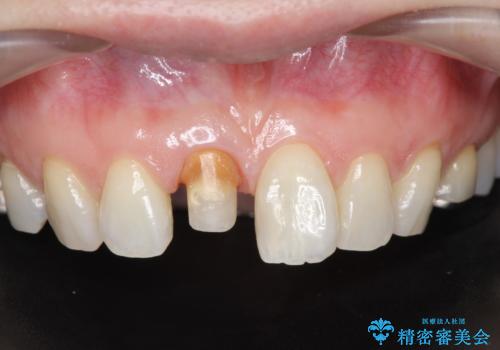

前歯の変色 セラミック審美補綴

- 前歯の変色の改善を希望され来院されました.

以前に神経が死に、根管治療を行った歯の変色が認められたためセラミックによる審美補綴治療を計画します。

神経の死んでいる歯について

神経治療を行い補綴(かぶせもの)治療を行わないと、変色が目立ち審美障害を起こすことがあります。

このような場合、セラミックによる審美改善が治療の一案として提案されます。